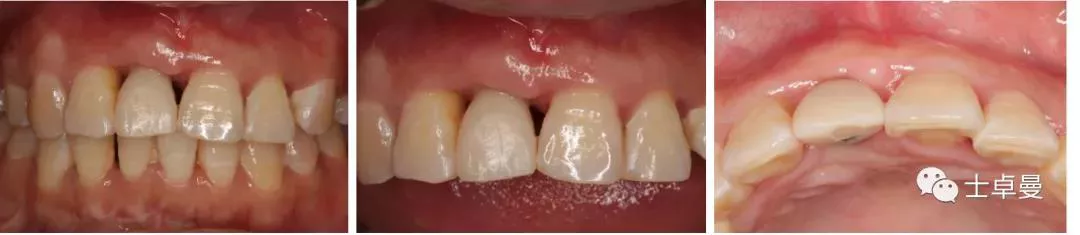

▷ 种植牙前检查(牙周系统治疗3个月后)口内检查

·      11缺失,拔牙创愈合良好,12松(Ⅰ-Ⅱ),21松(Ⅰ-Ⅱ),22松(Ⅱ),余留牙未见异常;

·      咬合正常,低位笑线,中厚龈生物型;

·      全口卫生状况良好,无牙结石。